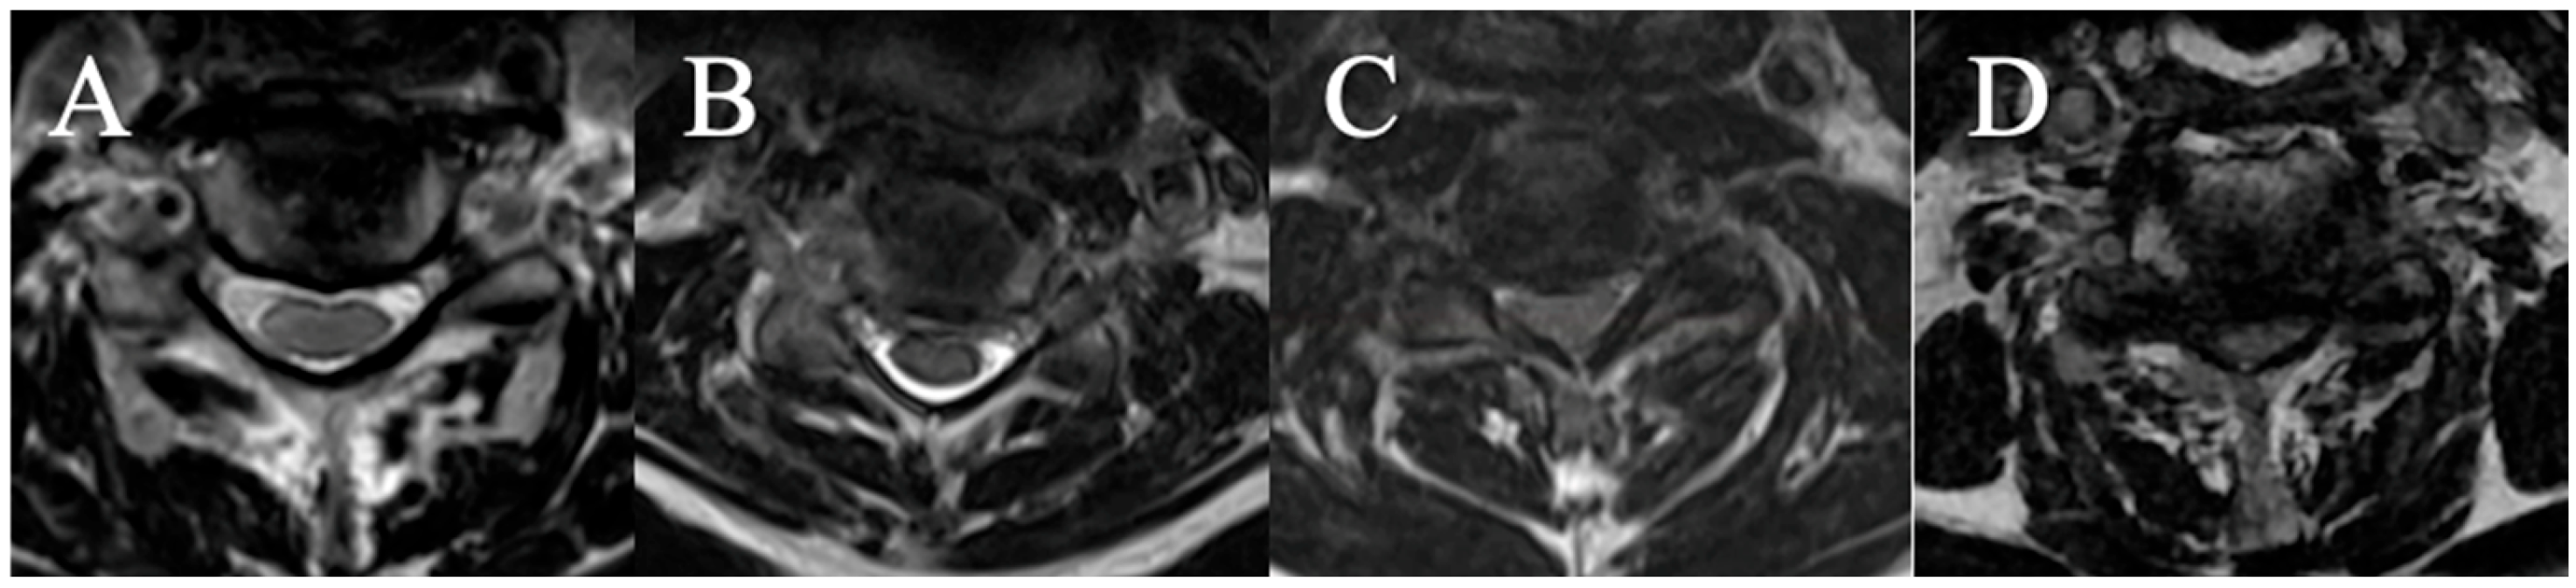

2.3.3. Cerebrospinal Fluid Cisterns

Four grades were selected on an axial slice (Figure 3)

(A) CSF visible anteriorly and posteriorly;

(B) CSF erased anteriorly or posteriorly;

(C) CSF erased anteriorly and posteriorly but root cisterns still visible;

(D) Totally erased cisterns—no CSF visible on the slice.

Figure 3. (A): CSF visible anteriorly and posteriorly; (B) CSF erased anteriorly or posteriorly; (C) CSF erased anteriorly and posteriorly but root cisterns visible; (D) totally erased cisterns.